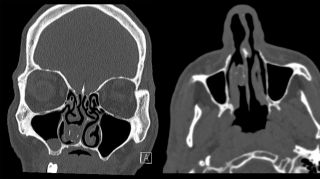

„48-letni mężczyzna został skierowany do Departamentu laryngologii Westmead po tym, jak tomografia komputerowa mózgu, pierwotnie wykonana z powodu bólu głowy, wykazała zwapnienie o wymiarach 19×11 mm w prawej jamie nosowej” – można przeczytać w raporcie opublikowanym przez lekarzy z Westmead Hospital w Sydney.